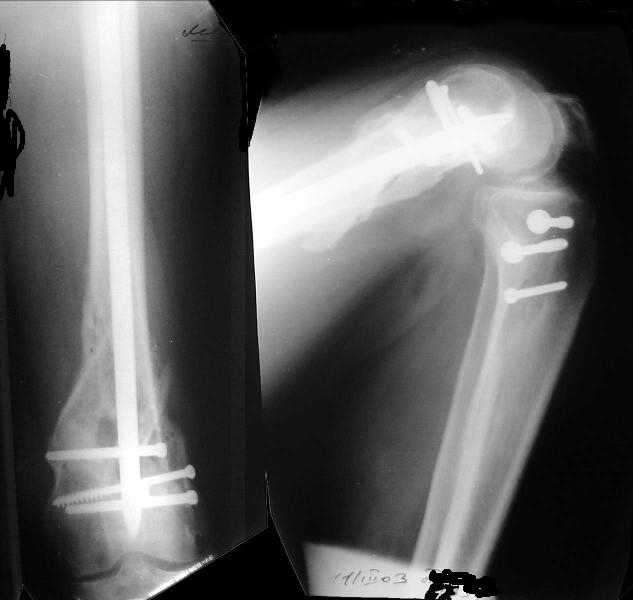

The mobilisation of knee is started immediately from the second day. Weight bearing is permitted as in any other interlocked nailing. That is, Toe touch to start with and within four days, partial to in another two weeks, full weight bearing. Of course that is assuming that the correct size nail has been used. Up to 70 kg body weight, 11no will be good enough and 12mm if more.Usually at the 1st followup, at 6 weeks time, they have full flexion..I

Enclosing a recent intraop picture